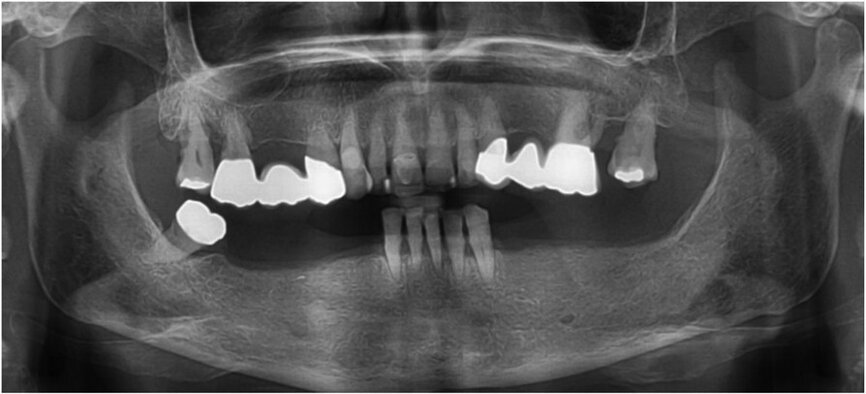

Fig. 1: Panoramic radiograph of the initial dental status.

The dental status showed acceptable oral hygiene and some teeth with Grade III mobility (teeth #41, 31, 32, 18 and 28) and local periodontal problems, including horizontal bone loss (teeth #42, 41, 31, 32, 33, 18, 17, 27 and 28). Teeth #42 and 33 were healthy and not mobile. The alveolar crest in the lateral mandible area showed clinically a wide shape with thick keratinised mucosa. The initial panoramic radiograph revealed stable crestal bone in the lateral mandibular area (Figs. 1–3). Thus, in the lower jaw, the single-tooth prognosis was fair for teeth #47, 42 and 33, and hopeless for teeth #41, 31 and 32.[24]